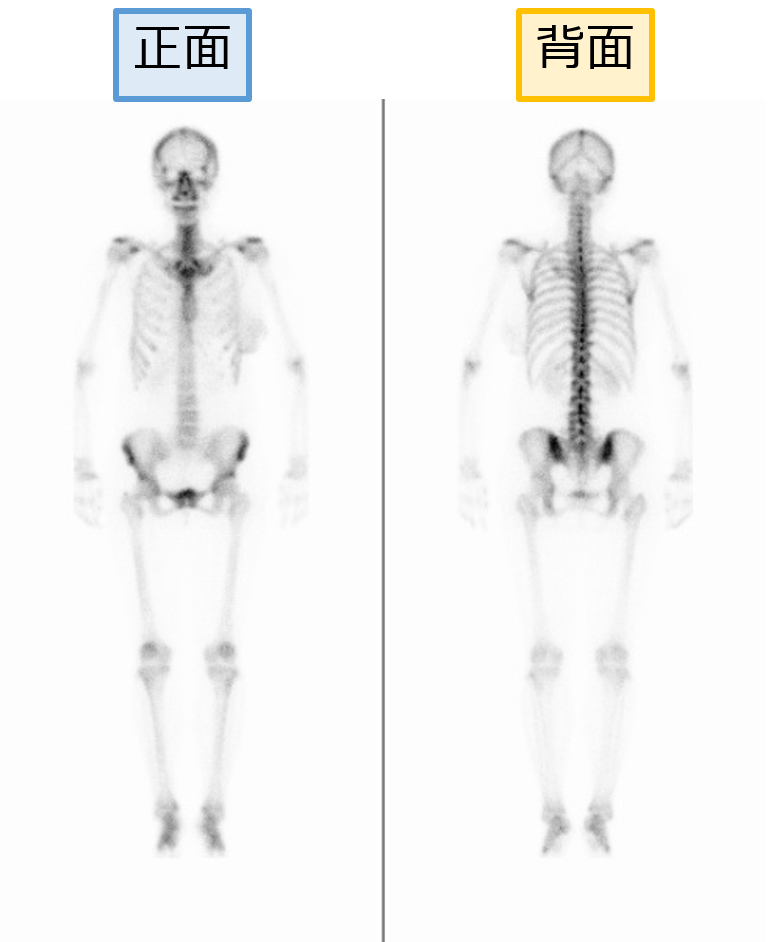

●骨シンチグラフィ

骨シンチグラフィ検査は、がんが骨へ転移しているかどうかを検出するのに頻繁に利用されますが、がんが骨に転移しているかどうかは、がんの治療を進めていくうえで重要な情報となります。

⇩拡大